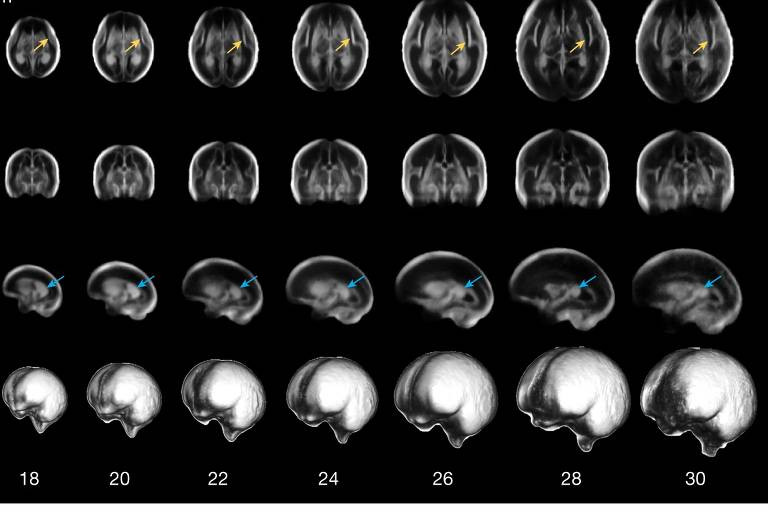

Faixa normativa do volume cerebral fetal derivado por ressonância magnética